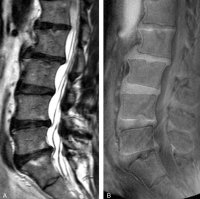

這次研究共有108名華南地區人士(平均年齡52歲,男女各半)參與。傳統的T2W MRI用作評估椎間盤退化和其他影像病徵,T1-rho MRI用作量度構成椎間盤的主要成份 “蛋白聚醣”水平。UDS 病徵被定義為在UTE MRI上檢測到的超高或超低光束帶。參與者的基本資料、病歷、腰背痛情況及活動能力指標(ODI Oswestry Disability Index)亦於研究時採納為臨床指標之一。

研究結果發現39.8%的參與者有UDS病徵,而其中61.4%的UDS是發生於下腰部位置。有UDS病徵比沒有UDS病徵的參與者有更多機會患有椎間盤退化、椎間盤突出、脊椎移位及椎體變異(Modic Change)。有UDS病徵的椎間盤的蛋白聚醣含量比沒有UDS的椎間盤低。而逾六成UDS病徵是無法在傳統的T2W MRI上檢測到。有UDS病徵的參與者比沒有的參與者有更嚴重的腰背痛,而同時其活動能力亦較差,而傳統的T2W MRI並無法找出此關連。研究更指出約四成患者於多節腰椎皆出現UDS病徵,其患上嚴重腰背痛的機率比單節腰椎出現UDS的患者更高。